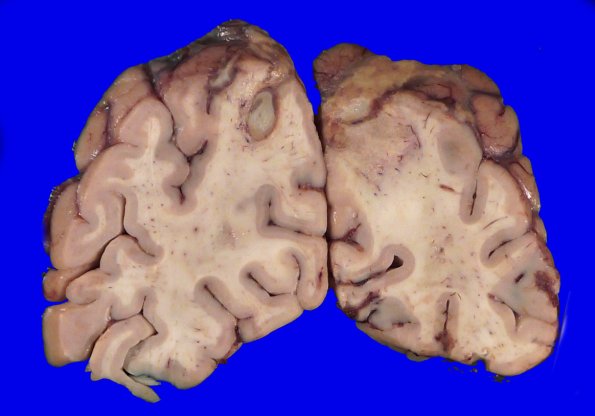

Washington University Experience | INFECTION | Fungus | Mucormycosis - Zygomycosis | 12B5 Abscess (Case 12) Gross_13

The gross specimens show striking numbers of lesions, frequently at gray-white junctions (if small, like 12B2), with hyperemic rims and purulent/necrotic content.